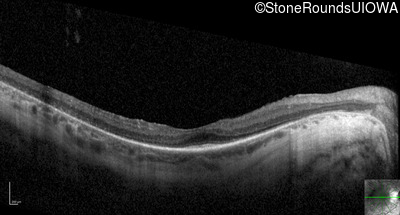

Optical Coherence Tomography - Right - 20/50 -2

Exemplar / OCT Stack

OCT Stack